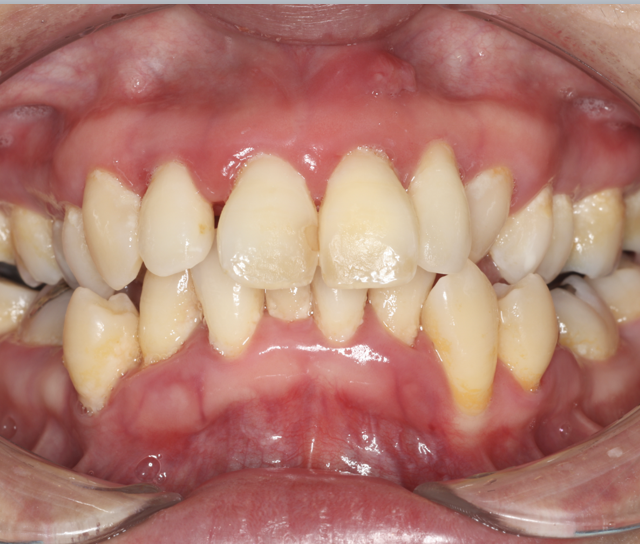

歯周病